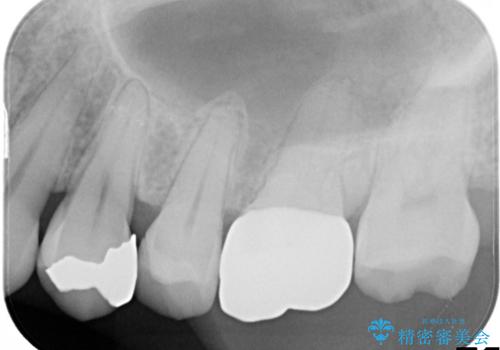

- 「何もしなくても歯が痛む、咬むと歯が痛む」を主訴に来院された患者さんです。検査の結果、歯髄の部分壊死と診断しました。根管治療を行いファイバーコアとオールセラミッククラウンで治療を行いました。

術前に神経の部分壊死と診断しましたが、神経をあけたときに出血が一切無かったので神経が死んでいるという診断は正しかったという事になります。

神経が死んでしまった原因はプラスチック(保険適用治療)の被せ物が劣化し歯と被せ物の間に生じた隙間からのリークが原因だと考えます。